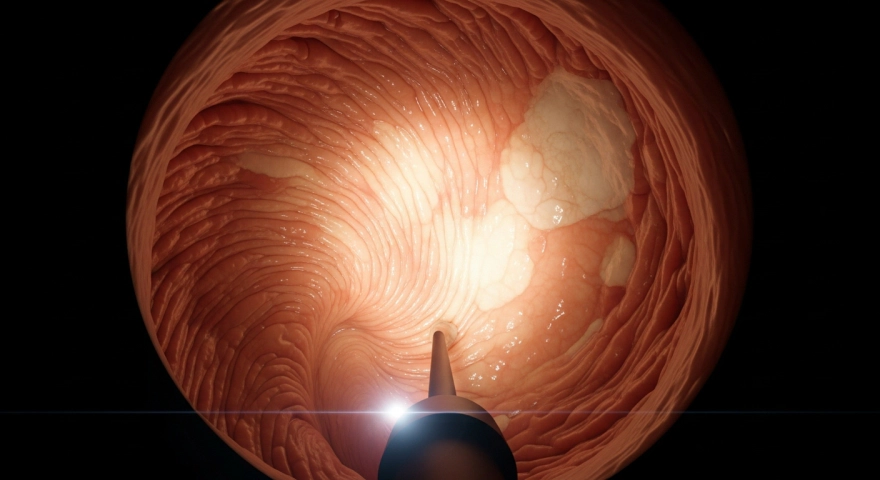

가장 정확한 방법은 위 내시경 검사입니다.

내시경을 통해 위 점막의 색, 구조, 위축 정도를 직접 눈으로 확인할 수 있어요.

필요 시 조직검사(생검)를 함께 시행하여 세포 상태를 확인하고,

헬리코박터균 감염 여부도 함께 진단할 수 있습니다.